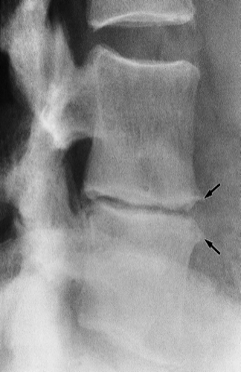

Disc space narrowing caused by disc degenerative changes between L3 and L4.

Note the osteophytes (arrows) and sclerosis of the adjoining surfaces of the vertebral bodies.